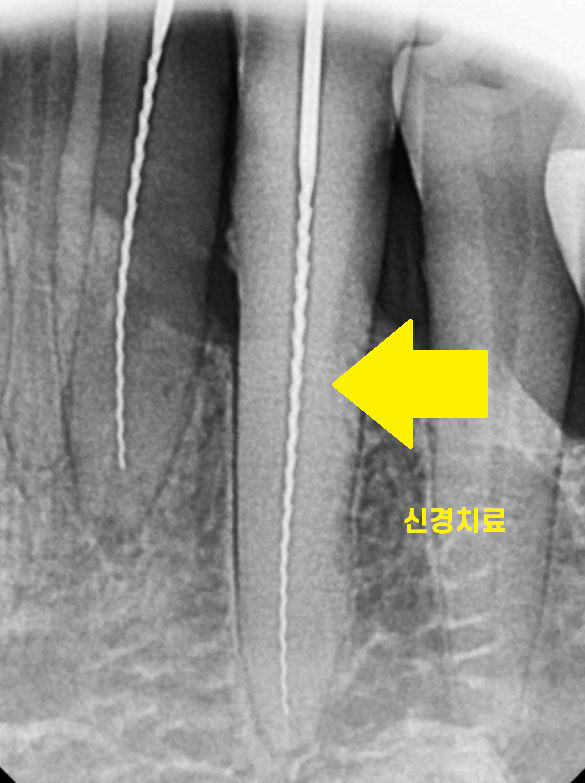

그 외에도 신경치료

신경의 길이도 재야하고

뿌리 염증이 사라졌는지 확인해야하니까 찍어야하고